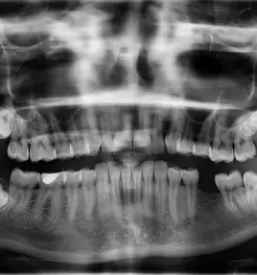

Naše delo je naše poslanstvo. Zavedamo se, kako pomembni so zdravi zobje za zdravje in samozavest posameznika, zato uporabljamo le najboljše materiale, aparate in pripomočke, kar lahko potrdi že veliko naših zadovoljnih strank in odličnih referenc. Dober privat zobozdravnik v Mariboru je sedaj na voljo tudi vam! Zavedamo se, da je strah pred obiskom zobozdravnika zelo pogost pojav, zato smo pri delu vedno nežni, razumevajoči in pristopamo brez kakršnegakoli obsojanja. Težave z zobmi se lahko pojavijo pri komurkoli - mi smo tukaj, da naredimo vse, kar lahko, da jih odpravimo.

Svoje znanje in izkušnje nenehno dopolnjujemo, sledimo novostim v zobozdravstvu tako doma kot po svetu in jih kot dober privat zobozdravnik v Mariboru uspešno vpeljujemo v svoje delo. Smo zanesljivi, odgovorni, prisluhnemo vašim željam in vam svetujemo glede na vaše stanje.

Ker smo dober privat zobozdravnik, Maribor že zelo dobro pozna naš pristop k delu in storitve, ki med drugim obsegajo: